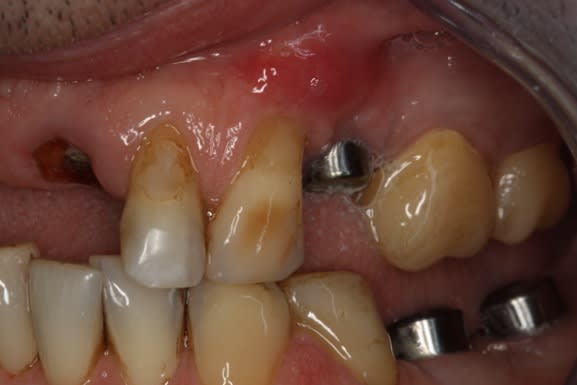

Je place pour la digue, utile en implanto aussi !

Patiente ref pour un bridge qui bouge..

Hop, 2 implants, comblement et provisoire

Je voulais faire une MCI, mais pas assez de nonos autour de la 32, j'aime pas le risque, suis très conservateur.